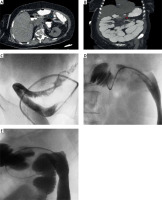

Figure 1

A – Anastomotic ileocolic stricture in the distal transverse colon (blue arrow). B – Transition point in the level of the ileocolic anastomosis (red arrow). C – 360° turn of the sigmoid colon overpassed with the Amplatz catheter. D – Guidewire passed through the ileocolic anastomosis, with contrast in the ileum. E – A stiff catheter is passed over the guidewire for better stability